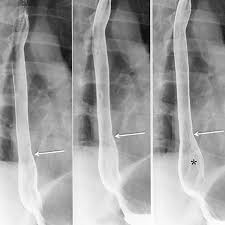

In normal digestion, the lower esophageal sphincter (LES) opens to allow food to pass into the stomach and closes to prevent food and acidic stomach juices from flowing back into the esophagus. Gastroesophageal reflux occurs when the LES is weak or relaxes inappropriately, allowing the stomach's contents to flow up into the esophagus.

GERD is caused by a failure of the lower esophageal sphincter. In healthy patients, the "Angle of His"—the angle at which the esophagus enters the stomach—creates a valve that prevents duodenal bile, enzymes, and stomach acid from traveling back into the esophagus where they can cause burning and inflammation of sensitive esophageal tissue.